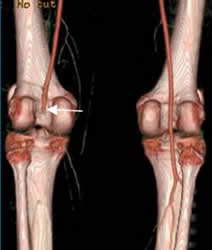

Fig 32. AngioTAC.

Otro caso de luxación complicada con oclusión de la poplítea derecha. Segmento femoropopliteo izquierdo normal.